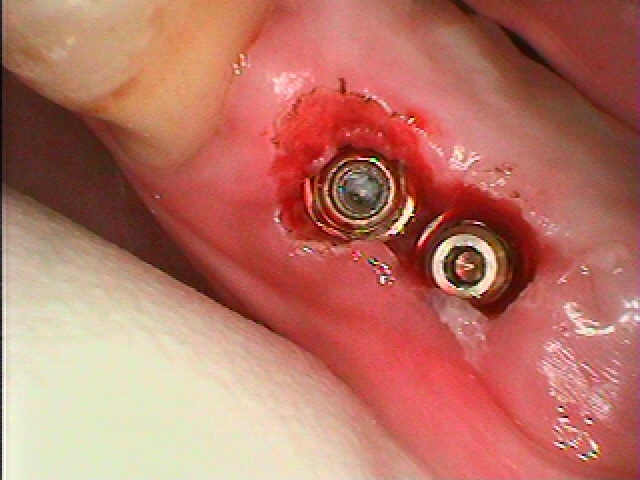

中のアバットメントを取り出してみます

角度とインプラント間が近接しておりかなりよくないです

患者さんはインプラントは取りたくないとのこと